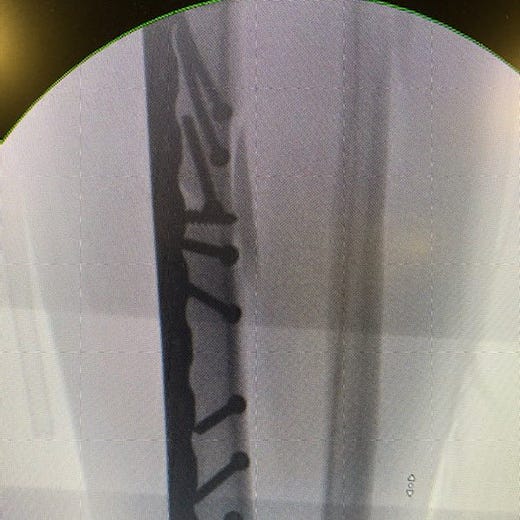

The next morning a long ambulance ride to Central Maine Medical in Lewiston. There a surgeon, a skier himself, amazed by my break – tibia and fibula. “Spectacular,” he called it. “You have strong bones. They resisted the break. When they broke, they exploded.” A spiral fracture splintering into what he called butterfly fragments. “Normally those are three or four millimeters long. Yours were 20. Just amazing.”

Surgery happened in an instant. At least for me, drugged and grateful to be a citizen of the future, of this amazing century with this impossible technology. Here is what he fixed: